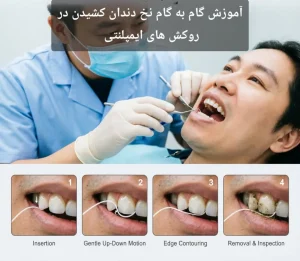

- استفاده از مسواک و نخ دندان مخصوص